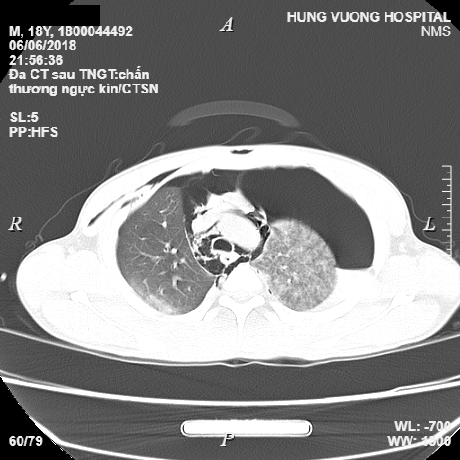

Hình ảnh tràn khí màng phổi rất nặng, xẹp hoàn toàn phổi trái.

Vào bệnh viện, bệnh nhân được chỉ định chụp CT đa dãy, kết quả chụp CT cho thấy hình ảnh tràn khí màng phổi rất nặng, xẹp hoàn toàn phổi trái, tràn khí nhiều dưới da vùng mặt cổ kèm theo gãy xương đòn phải, gãy đa xương sườn.